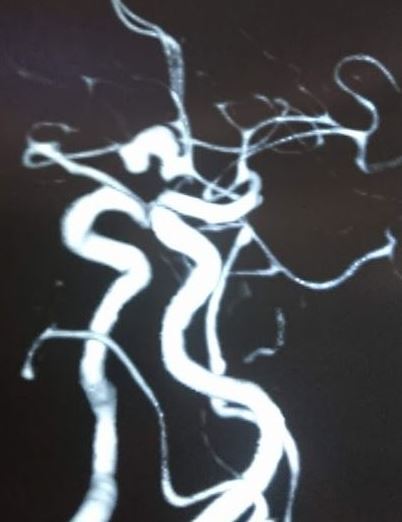

ሴሬብራል አኑኢሪዝም   Cerebral Aneurysm

ሴሬብራል አኑኢሪዝም በአንጎል ውስጥ ባለው የደም ቧንቧ ዝውውር ላይ በደካማ ቦታዎች ላይ የሚከሰቱ መዘዞች በመባል ይገለጻሉ። አብዛኛዎቹ ሴሬብራል አኑኢሪዜም ጸጥ ያሉ ናቸው እና በአጋጣሚ በኒውሮኢሜጂንግ ወይም በሬሳ ምርመራ ላይ ሊገኙ ይችላሉ። በግምት 85% የሚሆኑት አኑኢሪዜም በቀድሞው የደም ዝውውር ውስጥ ይገኛሉ ፣ በተለይም በዊሊስ ክበብ ውስጥ ባሉ መጋጠሚያዎች ወይም መጋጠሚያዎች ላይ። Subarachnoid የደም መፍሰስ (SAH) ብዙውን ጊዜ የሚከሰተው ከመጥፋት ጋር ሲሆን ከከፍተኛ የበሽታ እና የሞት መጠን ጋር የተያያዘ ነው. ይህ እንቅስቃሴ ሴሬብራል አኑኢሪዜም ያለባቸውን ታካሚዎችን በመንከባከብ የተውጣጡ ባለሙያዎች ቡድን ሚናውን ጎላ አድርጎ ያሳያል።

Cerebral aneurysms are defined as dilations that occur at weak points along the arterial circulation within the brain. The majority of cerebral aneurysms are silent and may be found incidentally on neuroimaging or upon autopsy. Approximately 85% of aneurysms are located in the anterior circulation, predominately at junctions or bifurcations along the circle of Willis. Subarachnoid hemorrhage (SAH) usually occurs with rupture and is associated with a high rate of morbidity and mortality. This activity highlights the role of the interprofessional team in caring for patients with a cerebral aneurysm.

ለምንጩ እና ለበለጠ መረጃ እዚህ ወይም ፎቶወቹን ይጫኑ Click here or on the images for source and to read more